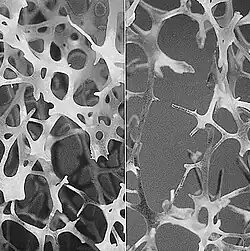

To diagnose osteoporosis, despite the inclusion of bone mineral density (BMD), biological markers and clinical factors of fracture risk, many not detected patients are at risk and many fractures are not explained. Bone mineral density is an assessment of the quantity of bone. It does not provide information on bone quality, another important parameter to describe the bone. In addition, clinical risk factors for fracture are at best an indirect assessment of the bone quality. One way to describe the quality of the bone is to assess its microarchitecture. Bone microarchitecture is related to the mechanical strength of bone and hence its greater or lesser risk of fracture. Indeed, for the same quantity of bone, different mechanically resistant bone structures may exist (few large trabeculae or numerous thin trabeculae that are mechanically stronger). Actually, bone loss is often accompanied by a deterioration of bone architecture, resulted in a decreased number of trabeculae, increased inter-trabecular distances, and a loss connectivity of the trabecular meshwork. Moreover, reduction of cortical bone thickness and increased porosity accompany trabecular bone loss, and in particular promote the fragility of the femoral neck. Osteoporotic bone is called "porous".

It was found that TBS is a reflection of the structural condition of the bone microarchitecture. TBS is strongly correlated with the number of trabeculae and their connectivity and negatively with the space between trabeculae.[2][3] That is to say that a high TBS value means that microarchitecture bone is dense, well connected with little spaces between trabeculaes. Conversely, a low TBS value means that the microarchitecture of bone is incomplete and poorly connected with wide spaces between trabeculae.[4]